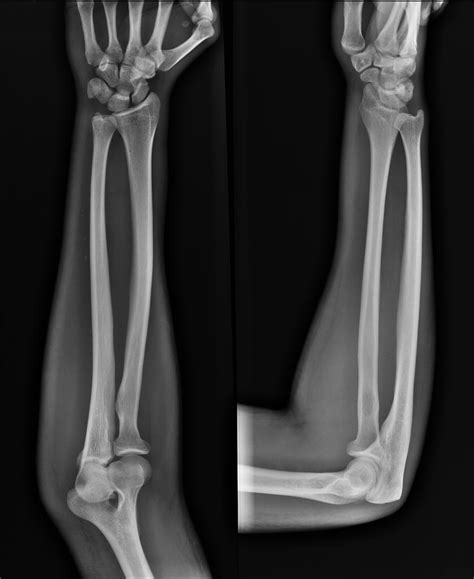

A forearm X-ray is one of the most common diagnostic imaging procedures performed in emergency departments, urgent care centers, and orthopedic clinics. Whether you have suffered a sudden fall, a sports-related injury, or are experiencing unexplained chronic pain, this imaging tool provides doctors with a vital, non-invasive look beneath the skin. By utilizing small amounts of electromagnetic radiation to create images of the bones in the forearm—specifically the radius and the ulna—medical professionals can accurately diagnose fractures, dislocations, and various other structural abnormalities. Understanding the procedure, why it is requested, and what the results mean can help demystify the process and prepare you for your visit to the radiology department.

The primary purpose of a forearm X-ray is to visualize the structural integrity of the bones between the elbow and the wrist. While your doctor may perform a physical examination, physical symptoms alone cannot always distinguish between a severe bruise, a ligament strain, and a bone fracture. An X-ray is the gold standard for ruling out serious injuries.

To interpret a forearm X-ray, it helps to understand the anatomy involved. The forearm consists of two long bones that work together to allow for flexibility and rotation:

The Radius: Located on the side of the thumb, the radius is the bone that primarily allows the forearm to rotate, enabling you to turn your palm up or down.

The Ulna: Located on the side of the pinky finger, the ulna is larger at the elbow and helps form the hinge joint necessary for bending the arm.

Injuries to these bones often occur during a "FOOSH"—an acronym for Fall On an Outstretched Hand. When you fall, the impact travels up through the wrist and can easily fracture either or both of these bones. Because they are anatomically linked, a fracture in one often causes structural stress or a corresponding dislocation in the other.

Anteroposterior (AP) View The arm is flat on the table, palm facing up, providing a front-to-back view of the radius and ulna.

Lateral View The arm is turned 90 degrees, showing the side profile of the bones to check for displacement or angling.

Once the forearm X-ray images are captured, they are sent to a radiologist—a doctor who specializes in interpreting diagnostic images. They will look for:

• Fractures: Whether the bone is broken completely, partially (a hairline fracture), or fragmented (comminuted fracture).

• Alignment: Checking if the broken ends of the bone are touching or if they have shifted.

• Dislocations: Ensuring the bones of the elbow and wrist remain properly seated in their joints.

• Pathology: In rare cases, the X-ray can reveal bone tumors, infections, or signs of bone diseases that may have weakened the structure.